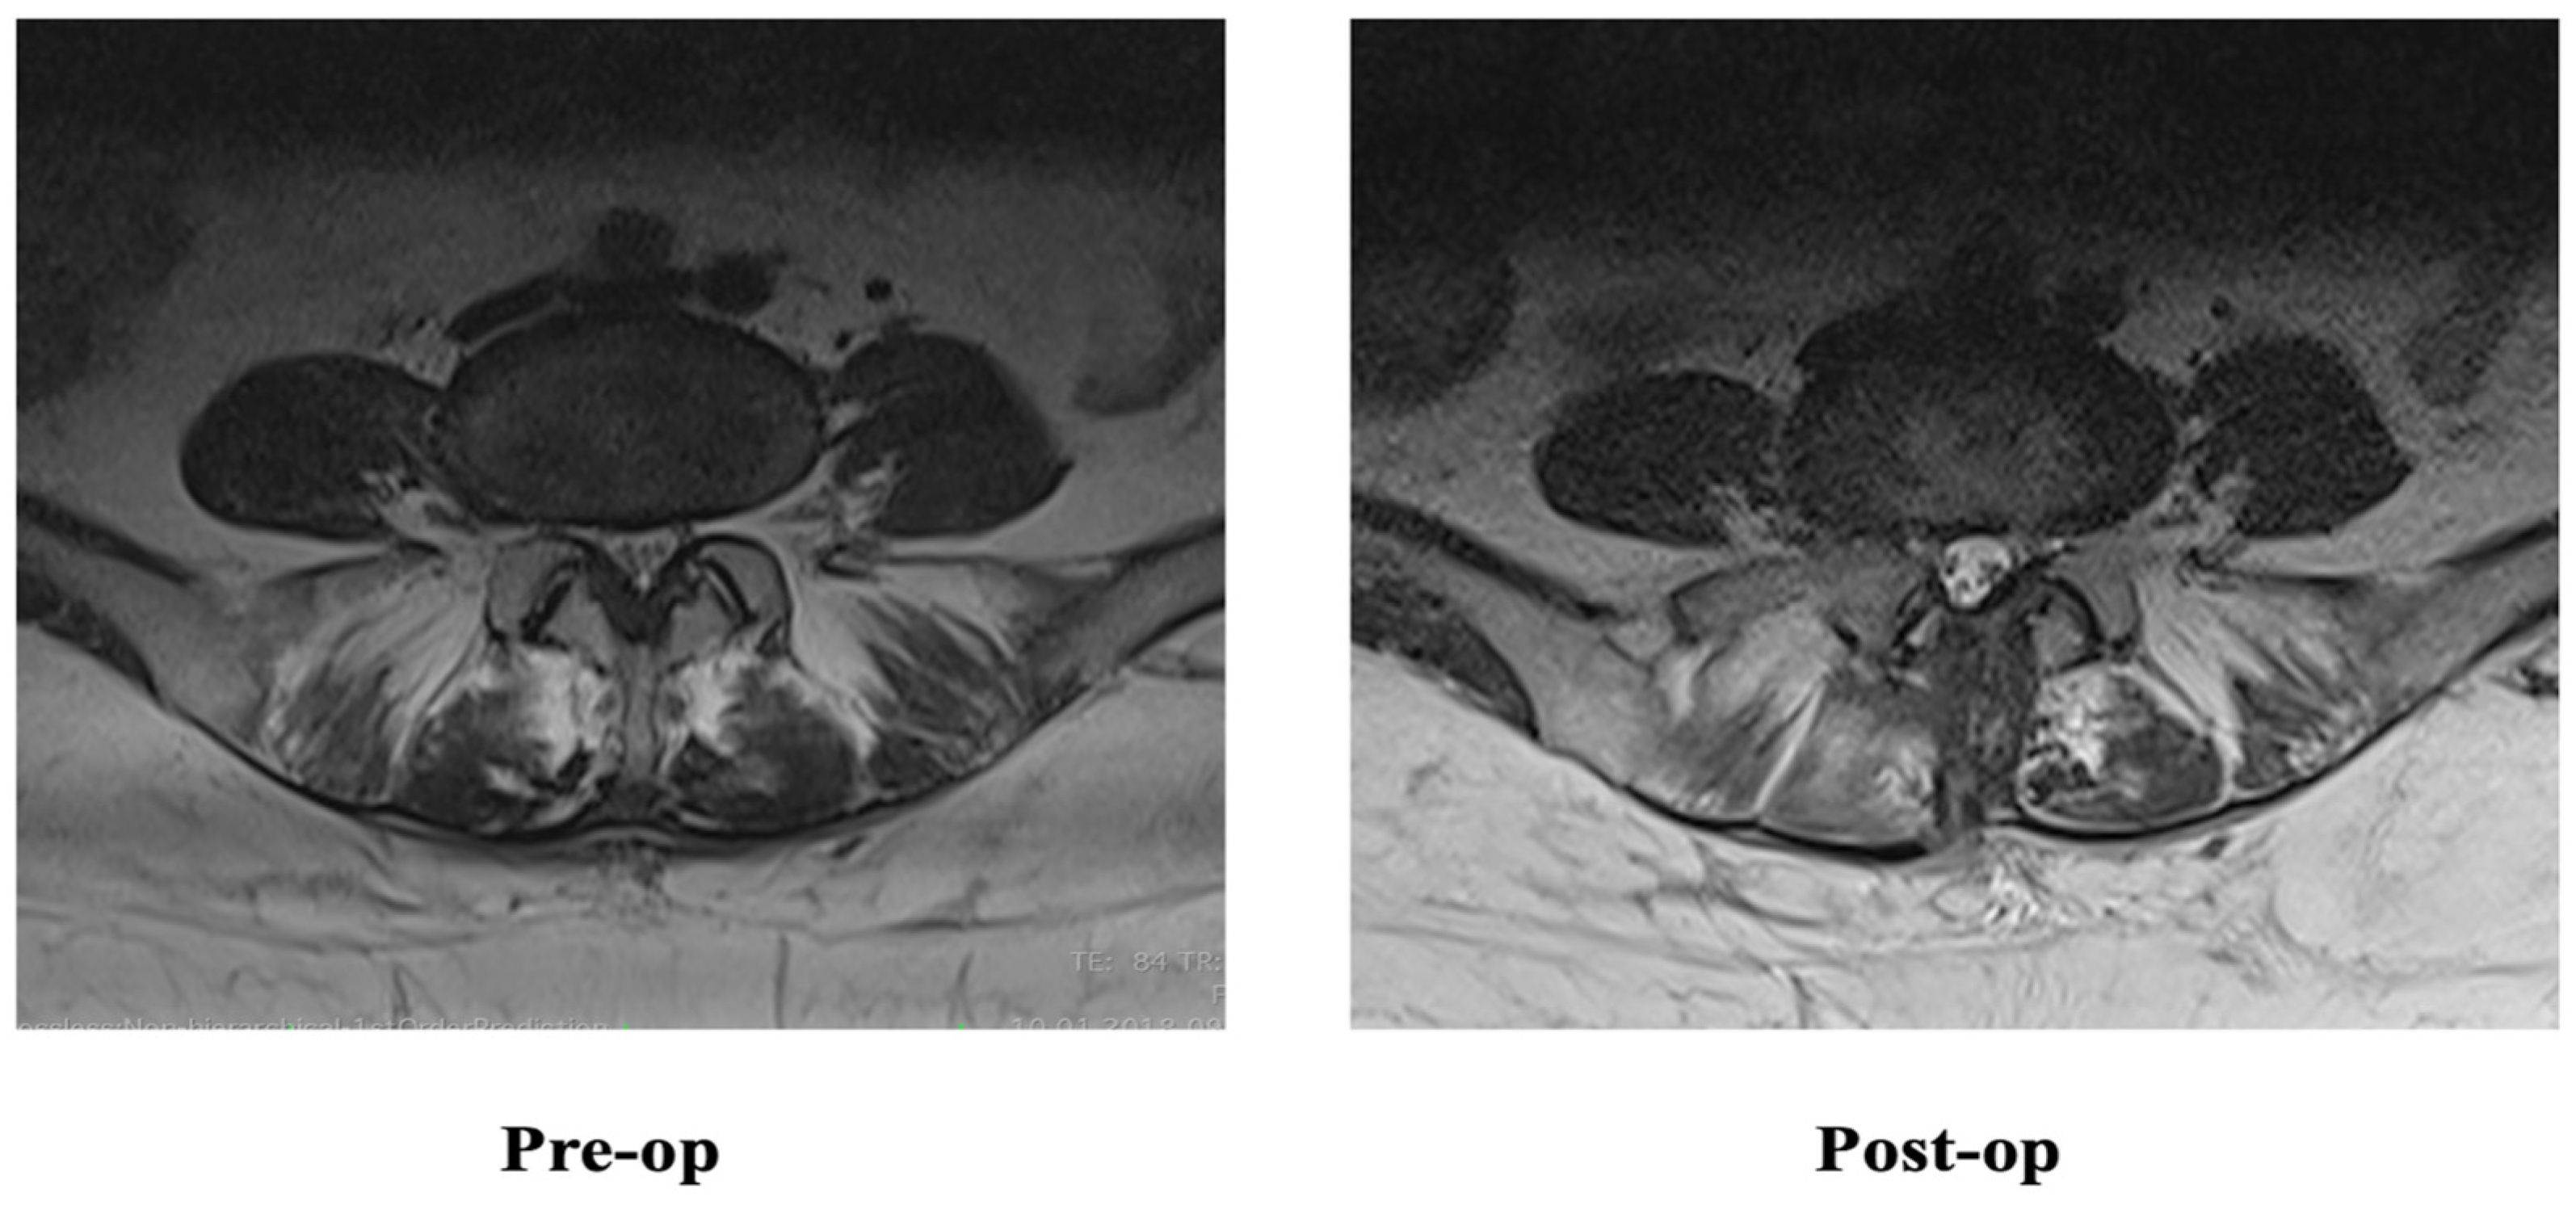

2.3. Radiological Evaluation

3.4. MFM CSA